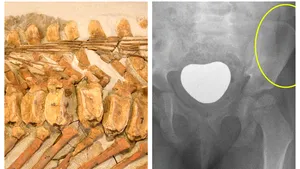

Premieră în lumea ştiinţei: o boală rară, veche de 66 de milioane de ani, care face victime azi, descoperită în fosila unui dinozaur

Cercetătorii de la Universitatea din Tel Aviv au descoperit în oasele unui dinozaur de acum 66 de milioane de ani, o tumoare rară care afectează oamenii în prezent, în special copii, relatează CNN. Oamenii de ştiinţă au observat găuri neobişnuite în două vertebre ale unei fosile de dinozaur din specia hadrosauride, descoperite în Canada.  Vertebrele […]